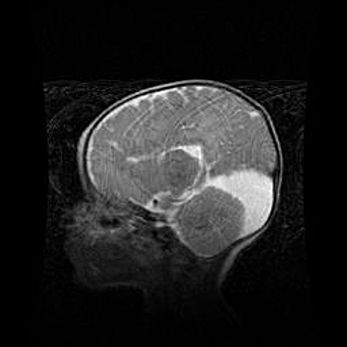

Сообщающаяся гидроцефалия. Кистозная энцефаломаляция головного мозга.

Возраст: 3 месяца 4 дня

Вес: 3100 г

Пол: женский

Окружность головы: 34 см

Срок гестации: 31 неделя

Кистозная энцефаломаляция головного мозга - одна из форм поражения головного мозга в детском возрасте. Характеризуется возникновением множественных и распространённых кист в коре, белом веществе и подкорковых образованиях головного мозга у плодов, новорождённых и детей раннего возраста. Развитие кистозной энцефаломаляции связано с внутриутробной асфиксией и гипотонией, родовой травмой, тромбозом синусов, пороками развития сосудов, инфекциями, сепсисом и другими причинами. Наиболее значимые инфекционные агенты: вирусы простого герпеса, цитомегалии, краснухи, токсоплазмы, энтеробактерии, золотистый стафилококк и другие.